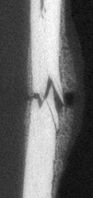

| Research GoalsSkeletal fracture is one of the most prevalent and costly medical issues in the United States, with direct costs exceeding $20 billion annually. In fact, some studies have shown that women over the age of 75 would rather be dead than suffer the consequences of a hip fracture. As a result, the overall goal of the Tomlinson lab is to determine novel mechanisms that augment bone strength and induce the rapid repair of skeletal fractures. In particular, the lab focuses on inflammatory signaling in the skeletal response to mechanical forces and damage using small animal models. The Role of NGF-TrkA Sensory Nerve Signaling in Bone Although sensory nerves are known to be present in mature bone, relatively little is understood about their function in the skeleton, aside from pain. In this project, we are investigating the role of NGF-TrkA signaling in sensory nerves. Nearly all of the nerves in bone express TrkA, the high affinity receptor for nerve growth factor (NGF). Furthermore, sensory nerves blanket the surfaces of bone in a mesh-like network, a privileged location for the acquisition of mechanical signals. Using both in vivo and in vitro methods, we have demonstrated that NGF is robustly expressed by mature osteoblasts in response to non-damaging mechanical loads. Inhibition of NGF-TrkA signaling impairs load-induced bone formation whereas administration of exogenous NGF increases relative bone formation rates. These effects appear to be facilitated through altered Wnt/β-Catenin signaling, which we are currently investigating by using mice which lack NGF in the osteoprogenitor and osteoblast lineages. In addition, we have identified a compound which may provide long-term activation of TrkA to increase load-induced bone formation without the painful side effects of NGF. 1. Tomlinson RE, Li Z, Zhang Q, Goh BC, Li Z, Thorek DL, Rajbhandari L, Brushart TM, Minichiello L, Zhou F, Venkatesan A, Clemens TL. “NGF-TrkA Sensory Nerve Signaling Coordinates Vascularization and Ossification of Bone”, Cell Reports 2016; 16(10):2723-35. PMID: 27568565. PMCID: PMC5014649 2. Tomlinson RE, Li Z, Li Z, Minichiello L, Riddle RC, Venkatesan A, Clemens TL. “NGF-TrkA Signaling in Sensory Nerves is Required for Skeletal Adaptation to Mechanical Loads in Mice”, Proceedings of the National Academy of Sciences 2017; 114(18):E3632-E3641. PMID: 28416686. PMCID: PMC5422802 3. Li Z, Meyers CA, Chang L, Lee S, Li Z, Tomlinson R, Hoke A, Clemens TL, James AW. “Fracture repair requires TrkA signaling by skeletal sensory nerves”, Journal of Clinical Investigation 2019 Dec 2;129(12):5137-5150. PMCID: PMC6877307. 4. Fioravanti G, Hua PQ, Tomlinson RE. “The TrkA agonist gambogic amide augments skeletal adaptation to mechanical loading”, Bone 2021 Jun;147:115908. PMCID: PMC8097708. NSAIDs in Stress Fracture Risk and Repair Non-steroidal anti-inflammatory drugs (NSAIDs) are the most commonly consumed medication in the world, with over 30 million daily users in the United States alone. NSAIDs are effective in reducing pain and inflammation by preventing the synthesis of prostaglandin E2 (PGE2) through the blockade of the cyclooxygenase (COX) enzyme isoforms, COX1 and COX2. However, PGE2 is part of an inflammatory signaling pathway that is known to be critical for load-induced bone formation. In collaboration with our partners at the US Army Research Institute of Environmental Medicine and the Rothman Institute, we have identified a clear link between NSAID usage and stress fracture susceptibility. Furthermore, we have observed in mice that NSAIDs may increase stress fracture risk through two independent mechanisms – diminished load-induced bone formation and decreased bone toughness. In addition, we have identified NSAIDs which can provide analgesia without affecting stress fracture risk or repair. We are currently analyzing the mechanisms by which NSAIDs affect the skeleton, with the aim of uncovering novel therapeutic targets for relieving musculoskeletal pain without affecting bone health. 1. Park J, Fertala A, Tomlinson RE. “Naproxen impairs load-induced bone formation, reduces bone toughness, and diminishes woven bone formation following stress fracture in mice.” Bone 2019; 124:22-32. PMID: 30998998 2. Johnston TE, Dempsey C, Gilman F, Tomlinson R, Jacketti A, Close J. “Physiological Factors of Female Runners With and Without Stress Fracture Histories: A Pilot Study.” Sports Health 2020;12(4):334-340. PMID: 32525466 3. Staab JS, Kolb AL, Tomlinson RE, Pajevic PD, Matheny RW, Hughes JM. “Emerging evidence that adaptive bone formation inhibition by non-steroidal anti-inflammatory drugs increases stress fracture risk”, Experimental Biology and Medicine 2021; Feb 27. PMID: 33641442 NSAIDs in Dental Implant Osseointegration The use of dental implants has transformed the practice of dentistry over the last few decades. The success of this procedure relies on osseointegration, the process by which bone forms a structural and functional connection with the implant over a period of weeks to months. A significant portion of implants fail to osseointegrate, requiring additional surgical intervention. As a result, identifying factors that delay or prevent the osseointegration of dental implants is a top research priority. We hypothesize that use of NSAIDs in the immediate post-operative period may inhibit osseointegration of dental implants. This hypothesis may help explain idiopathic early failure of dental implants, since standard post-operative care often includes immediate and continuous use of high-dose NSAIDs. To directly test our hypothesis, we have assembled a research team of oral surgeons and orthopaedic basic scientists to generate quantitative data from newly placed dental implants as well as analyze bone tissue to ascertain the events that lead to early implant failure. This project is supported by an Osteo Science Foundation grant, in collaboration with our partners in Oral and Maxillofacial Surgery. Bioprinting Vascularized Bone Grafts The main cause of large bone graft failure is poor vascularization which leads to inner graft necrosis. Although this issue has been recognized for some time, developing bone grafts with adequate vascular function has proven to be a difficult problem to address and has prevented the widespread clinical use of engineered bone constructs. In this research area, we utilize 3D bioprinting to generate vascularized bone graft using patient-specific imaging data. First, we are developing a new computational tools to provide semi-automated generation of vascular structures within volume generated from standard clinical imaging. Next, we are optimizing the parameters used for extrusion bioprinting to improve outcomes and reproducibility using a type II fuzzy system. Our ultimate goal is to use bioprinting to generate patient-specific vascularized bone grafts for repair of carpal bones and other small bones with complex geometry and articulating surfaces. 1. Sedigh A, DiPiero D, Shine KM, Tomlinson RE. "Enhancing Precision in Bioprinting Utilizing Fuzzy Systems", Bioprinting. 2022 March. doi: 10.1016/j.bprint.2021.e00190. 2. Morrison DG, Tomlinson RE. “Leveraging advancements in tissue engineering for bioprinting dental tissues”, Bioprinting. 2021 Aug;23. doi: 10.1016/j.bprint.2021.e00153. Epub 2021 Jun 13. PubMed PMID: 34268456; PubMed Central PMCID: PMC8276871. 3. Sedigh A, Akbarzadeh-T MR, Tomlinson RE. "Comparison of Type-1 and Type-2 Fuzzy Systems for Mineralization of Bioprinted Bone", bioRxiv. 2021 March. doi: 10.1101/2021.03.31.437908. 4. Sedigh A, Tulipan JE, Rivlin MR, Tomlinson RE. "Utilizing Q-Learning to Generate 3D Vascular Networks for Bioprinting Bone", bioRxiv. 2020 October. doi: 10.1101/2020.10.08.331611. Other Research AreasCheck out our Publications. |